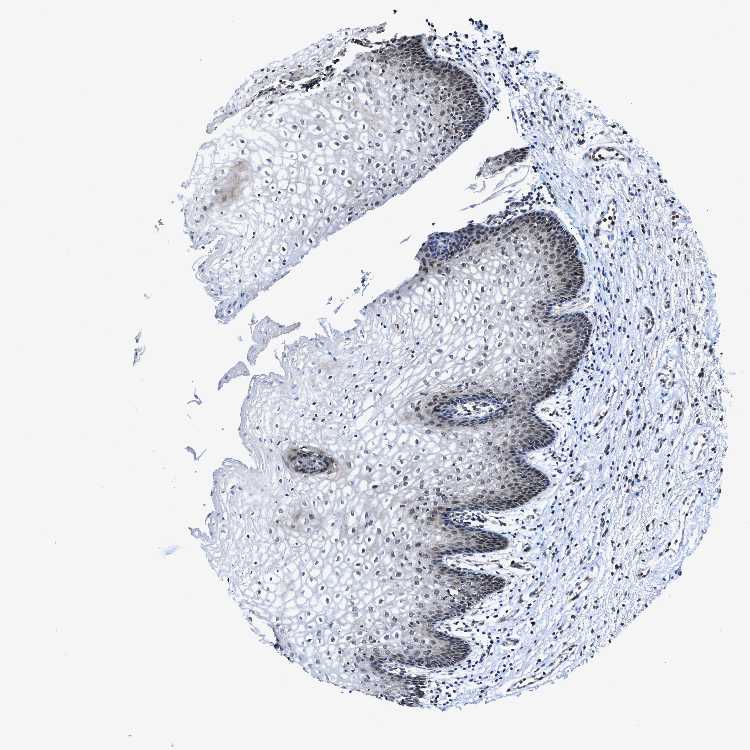

TISSUE PRIMARY DATA VAGINA Show tissue menu

VAGINA - Antibody stainingi

Antibody staining in the annotated cell types in the current human tissue is reported as not detected, low, medium, or high, based on conventional immunohistochemistry profiling in selected tissues. This score is based on the combination of the staining intensity and fraction of stained cells.

Each image is clickable and will lead to virtual microscopy that enables deeper exploration of all samples and also displays staining intensity scores, fraction scores and subcellular localization as well as patient and tissue information for each sample.

Antibody HPA020730Antibody HPA024251

Squamous epithelial cells LowMedium